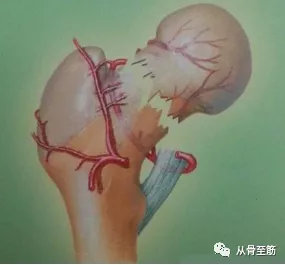

骨折断端局部血液供应情况:骨折部位有充足的血液供应被认为是最重要的因素之一。所以血供较差的部位如:腕舟骨,胫骨中下段,股骨颈等,骨折愈合较慢,很容易形成骨折不愈合。